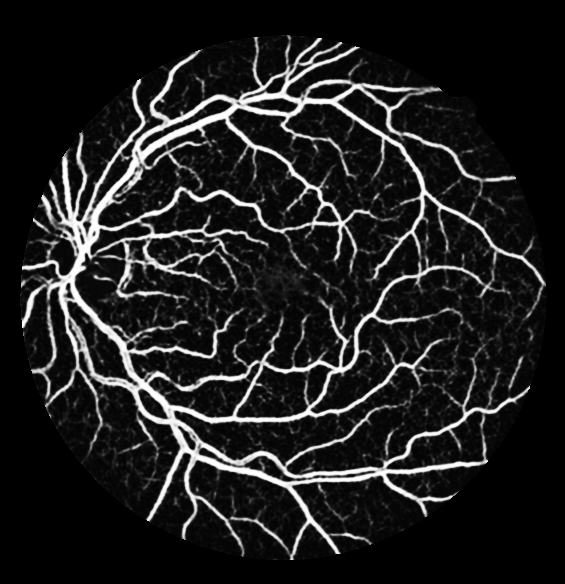

The evaluation of each experiment over the five different initialization roll-outs are reported in Table 1-4. The mean and standard deviations of five commonly used metrics, namely specificity, sensitivity, F1 score, accuracy and the AUC score are presented. The threshold for binarization is selected such that the F1 score is maximized on the validation sets. The threshold independent AUC score is chosen as the main performance indicator. The output probability maps of the degenerated trials are presented in Fig. 2 (c-f).

Table 1 shows that the AUC scores of additive U-Net variants fluctuate merely on the fourth digit, meaning that the expected performance boost is missing. The reduced number of convolutional layers in each level impairs the network marginally, while the absence of non-linearity has an impact on the performance. As for the subtractive experiment series with decreasing numbers of network levels in Table 2 and initial filters in Table 3, surprisingly not until the U-Net contains only one level and collapses into a sequence of convolution layers, or the number of initial filters drops to one, the segmentation results remain satisfactory with an AUC score above 0.97. In respective of the generalization study as reported in Table 4, a monotonous AUC score decline is observed with reducing amount of training subsets, in accordance with our prediction. However we did not anticipate that two sets for training already achieves an AUC score above 0.96, which indicates that the default U-Net has a high generalization capability in retinal vessel segmentation on DRIVE database.